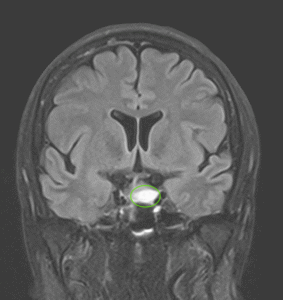

- RMN cerebral cu contrast este metoda de elecție pentru vizualizarea tumorii.

- Macroadenoamele hipofizare apar ca mase tumorale cu priza de contrast localizate la nivelul șeii turcești, eventual cu extensie superioară (supraselară) spre nervii optici sau, mai rar, inferioară, în sinusul sfenoid; de multe ori ele se pot extinde și lateral, în sinusurile cavernoase (structuri vasculare venoase formate în grosimea meningelui care mărginește lateral șaua turcească, prin care trec arterele carotide interne).

- Microadenoamele necesită un tip special de examinare RMN, cu secvențe repetate (în dinamică) realizate după administrarea substanței de contrast. Ele apar de obicei ca niște defecte de umplere – mici zone ne-gadolinofile (glanda hipofiză normală capteaza contrast mai repede decât adenomul); alteori singurul indiciu despre existența și localizarea adenomului (în afară de analizele hormonale) îl constituie asimetria glandei cu devierea tijei hipofizre de partea opusă